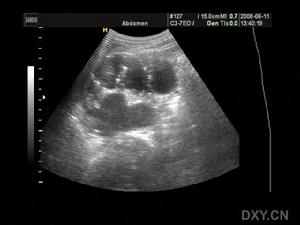

肾脏B超

renal abscess